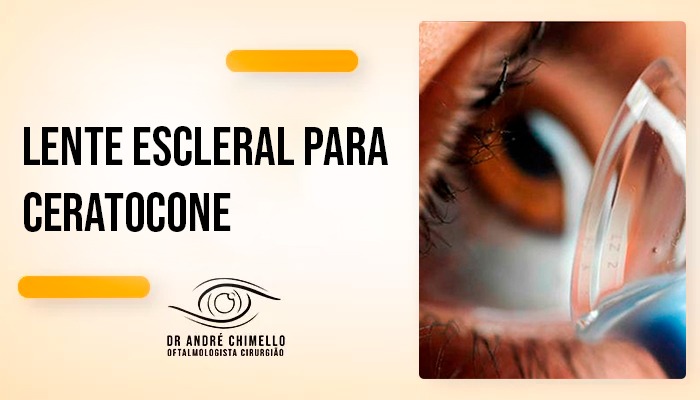

As lentes esclerais são maiores do que as lentes tradicionais e se apoiam na esclera (a parte branca dos olhos), sem tocar diretamente a córnea. Isso garante muito mais conforto e estabilidade visual. Além disso, formam um reservatório de lágrima entre a lente e a córnea, o que ajuda a proteger o olho e melhorar a lubrificação — ideal para quem também sofre com olho seco.